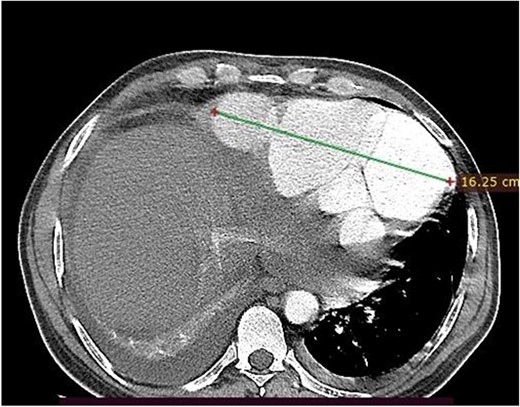

Axial image, just below the lower level of the heart, shows a 16 cm septated pseudoaneurysm that enhances with contrast.

With diagnosis of embolic stroke and LV pseudoaneurysm, he was stabilized in cardiac intensive care unit, and then operated via median sternotomy. Pericardium appeared edematous and darkened because of underlying hematomata. To prevent uncontrolled bleeding, extrapericardial cannulation was done on ascending aorta. Then pericardium covering right atrium was then opened and superior vena cava was cannulated and bypass was initiated. When pericardium over the pseudoaneurysm was then opened, there was a huge cavity measuring about 16 cm transverse and 10 cm vertically, which had pushed the heart upward. There was some thrombus inside. It was freely communicating with inferior wall of LV close to apex through a 2 cm rupture. The cavity wall and coagulated hematoma were removed and perforation repaired with Dacron patch (see Fig. 3). Chest tube and mediastinal tube were left and sternum was closed. He had smooth postoperative course with normal postoperative echocardiography. He stayed for 12 days in the ICU and was discharged on 18th postoperative day. He did not require any cardiac medications.